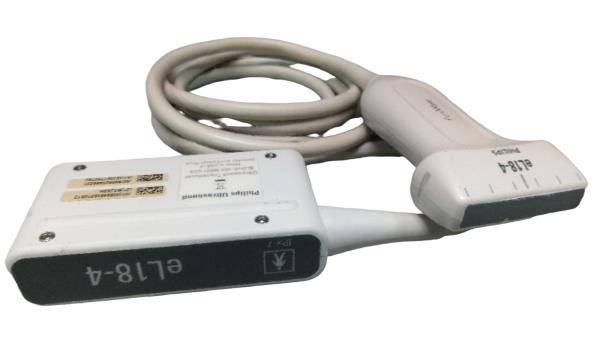

Philips x4 Ultrasound Probe Transducer 2003

Sale price$ 1,638.36

DIAGNOSTIC ULTRASOUND MACHINES FOR SALE

Philips x4 Ultrasound Probe Transducer 2004

Sale price$ 1,310.68